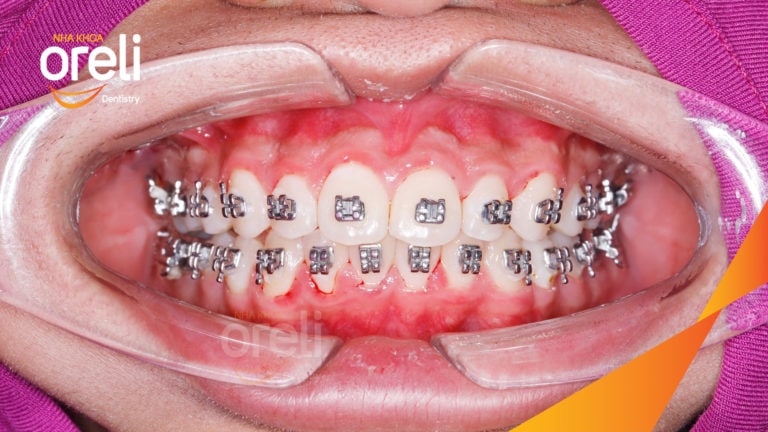

Ca niềng chỉnh cắn sâu hô lùi cằm cho kết quả nụ cười và góc nghiêng đẹp ở Oreli Niềng răngCắn sâuHôLùi cằm Xem thêm